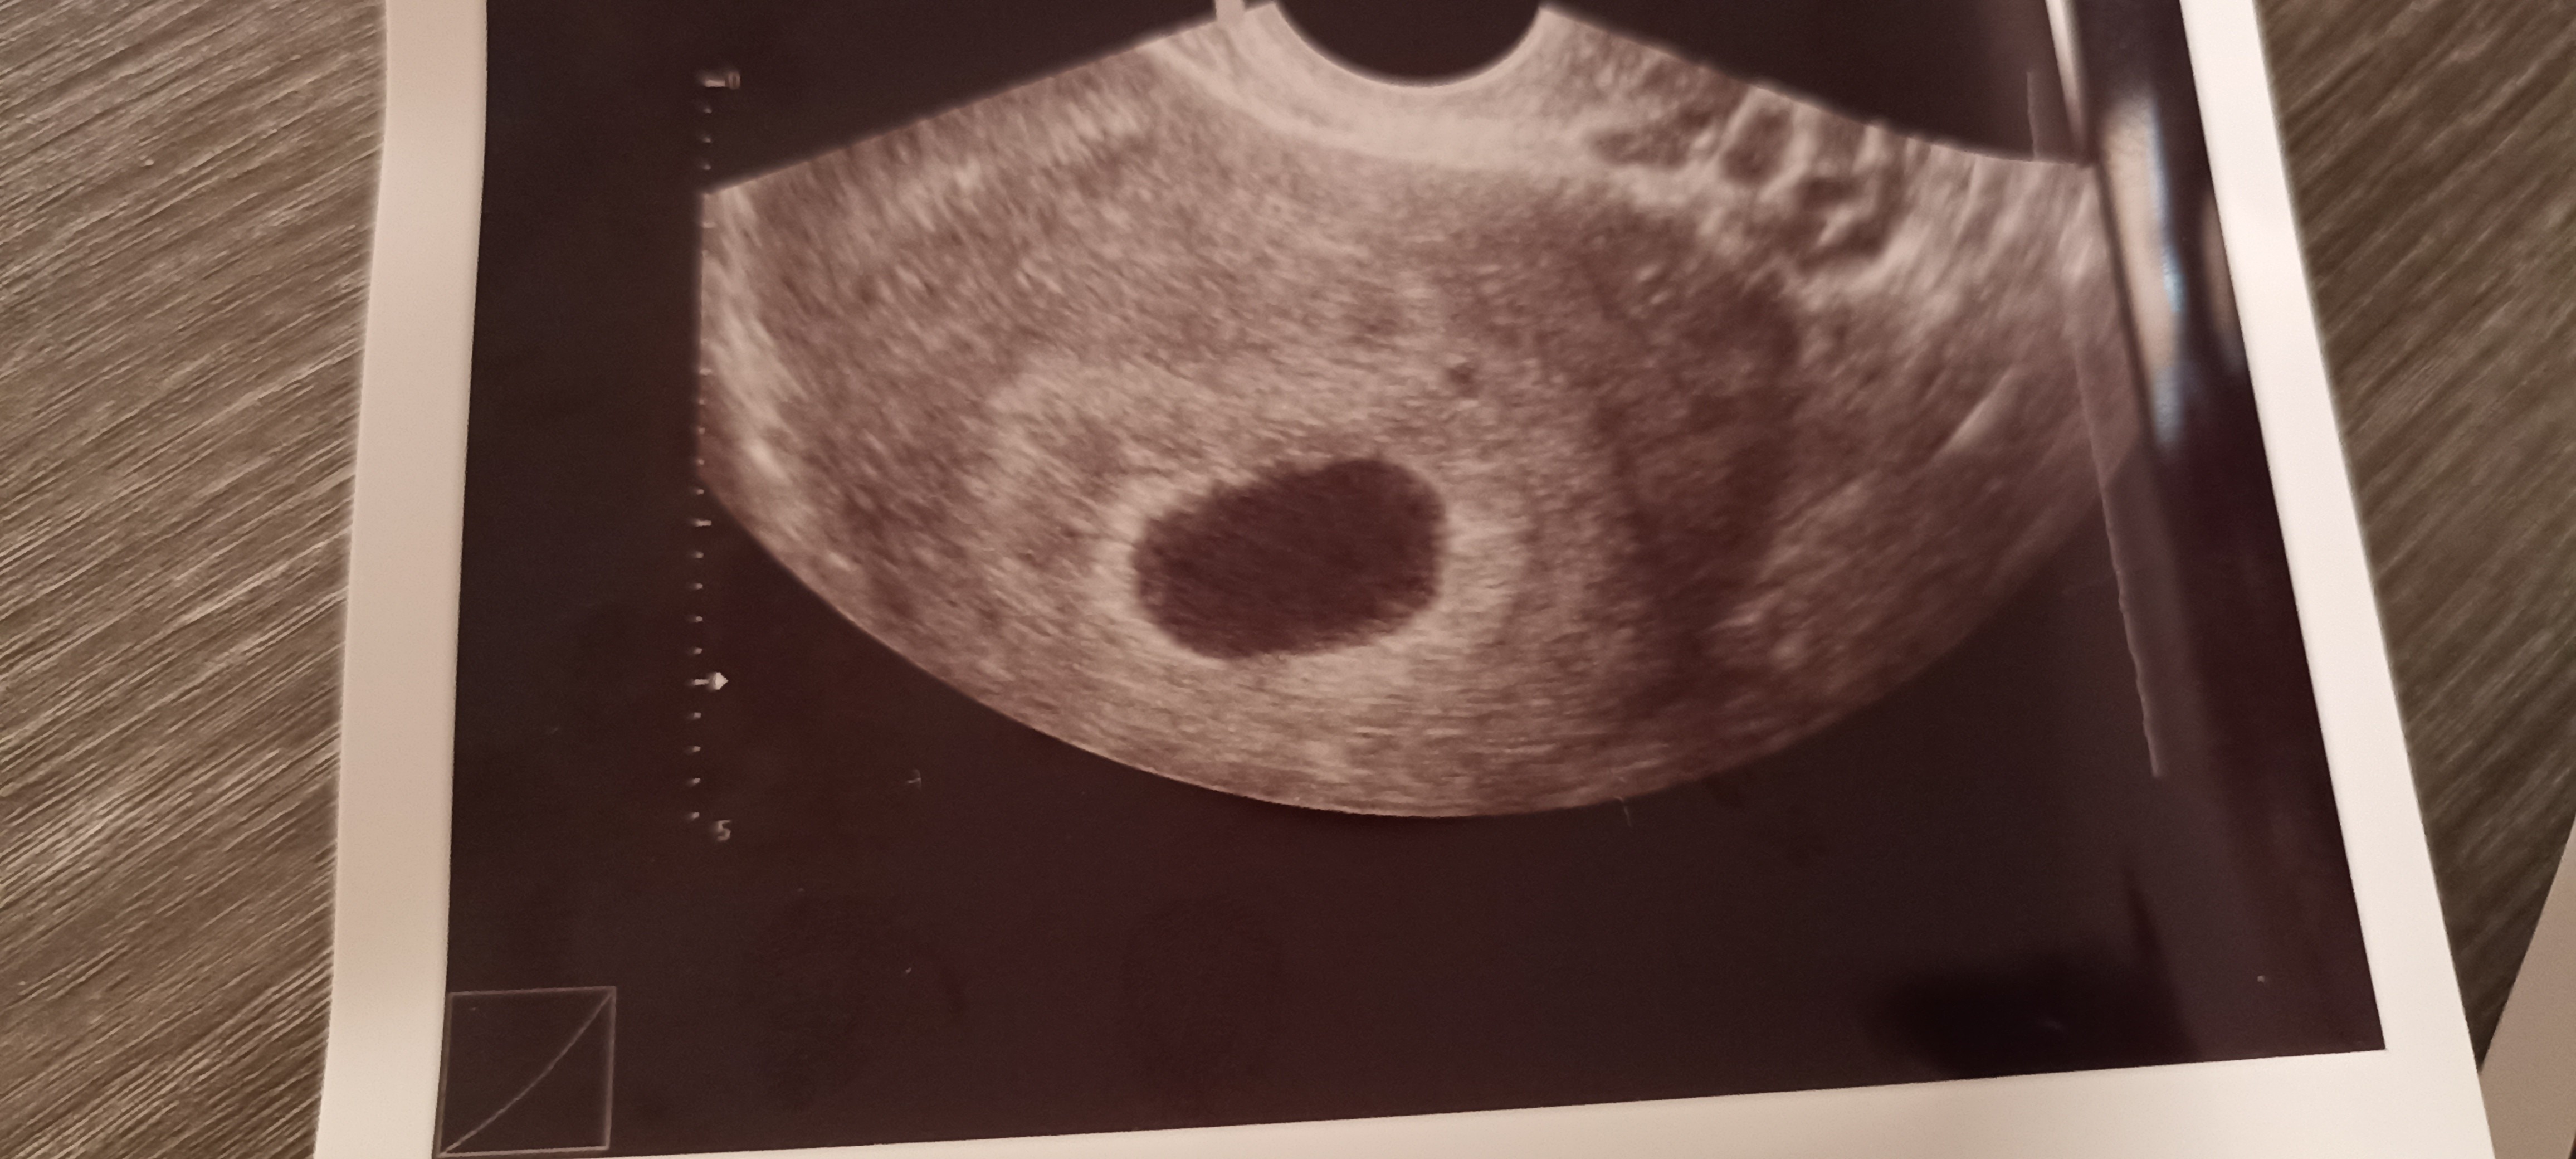

A to z mojego skanu (25/09)

Witam , jestem w Uk - stad moje mega obawy chyba. Ostatnia miese miałam 7/08. Test pozytywny 4/09 w dzień spodziewanej miesiączki. Według obliczeń poszliśmy na usg w 7+6 tyg (25.09). Babeczka robiąc usg wykryła puste jajo płodowe z nawiązką krwi obok jaja. Powiedziała ze może to być puste, małe jajo płodowe albo 5 tydz ciąży dopiero, z tym ze nie jest widoczne ciałko żółte. Dwa dni po badaniu plamienia różowe , potem brązowe, bol brzucha pojechaliśmy do szpitala - dalej pusto ale mówią , plamienia to normalka, bol brzucha to normalka No i czekać za dwa tyg scan. Według moich obliczeń mega niemożliwością jest żebyśmy byli w piątym tyg dopiero bo sex uprawialiśmy 19/08 (20/08 wypadała ovulacja) prosze bez ocianiania ale potem nie mieliśmy sexu do 3/9 dzień nastepny robiłam test który wyszedł pozytywnie. Ja rozumiem ze może się wszystko poprzesuwać ale cykle mam co 28 dni, regularne. No i te plamienia teraz z bolącymi plecami i podbrzuszem. Zamartwiam się totalnie. Mial ktoś taka sytuacje ? Kiedy wszystko wydaje się kalendarzykowo a jednak te 2 wielkie tyg wszystko się przesunęło ??